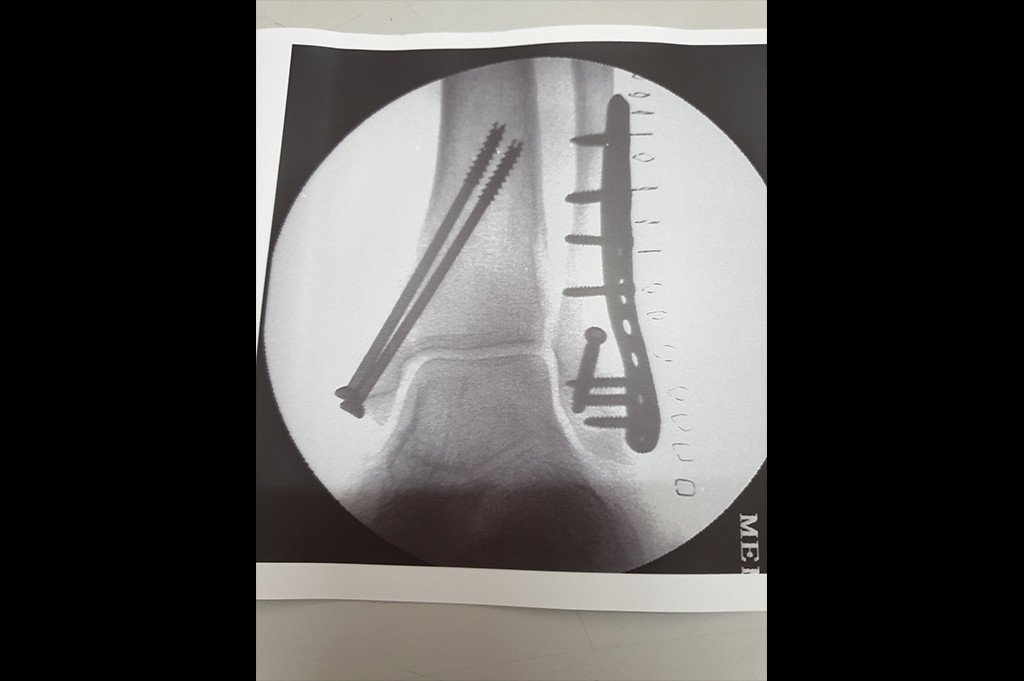

Ankle